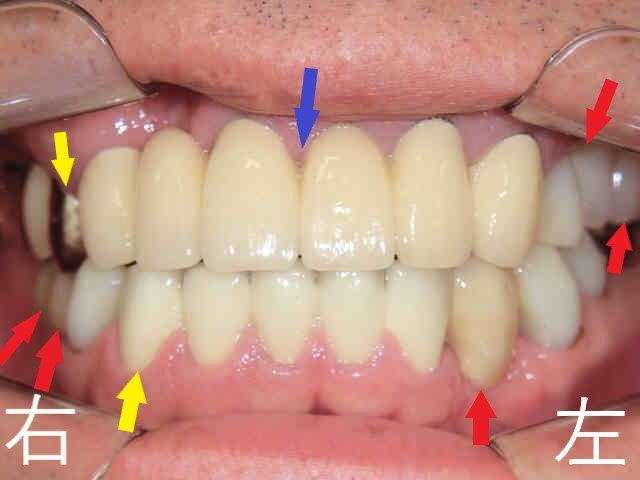

口腔内初診時の状況

《上顎の状態》

前歯には歯冠修復物(いわゆる差し歯)が装着されていたものの、多くの歯に重度の虫歯が確認され、一部の歯は残根状態(歯根のみが残った状態)でした。

《咬合状態の問題》

正面からの口腔写真では、上顎前歯が下顎前歯よりも内側に位置しており、反対咬合(いわゆる「受け口」)の状態が見られました。このような咬合の崩壊は、元々の骨格的要因か、もしくは後天的な歯列変化によるものか、診断を慎重に行う必要がある難症例です。